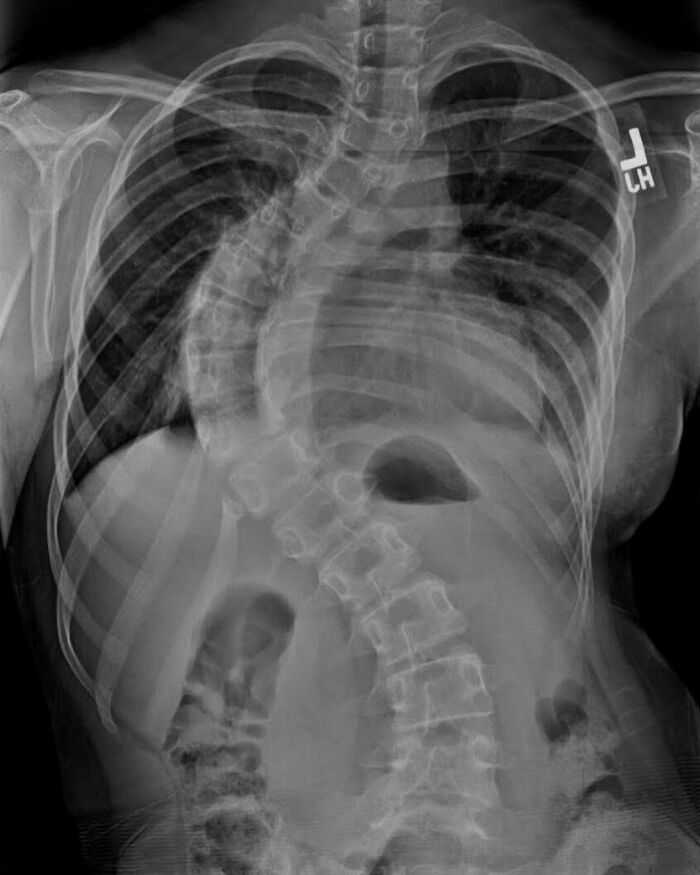

#4

Chest x-ray of a patient demonstrates a large left sided pulmonary cavity with a small dependent air-fluid level within the left mid zone, in keeping with pulmonary abscess. Patchy airspace opacification more inferiorly within left lower zone.

Scarring/atelectasis within lateral aspect of right upper zone.